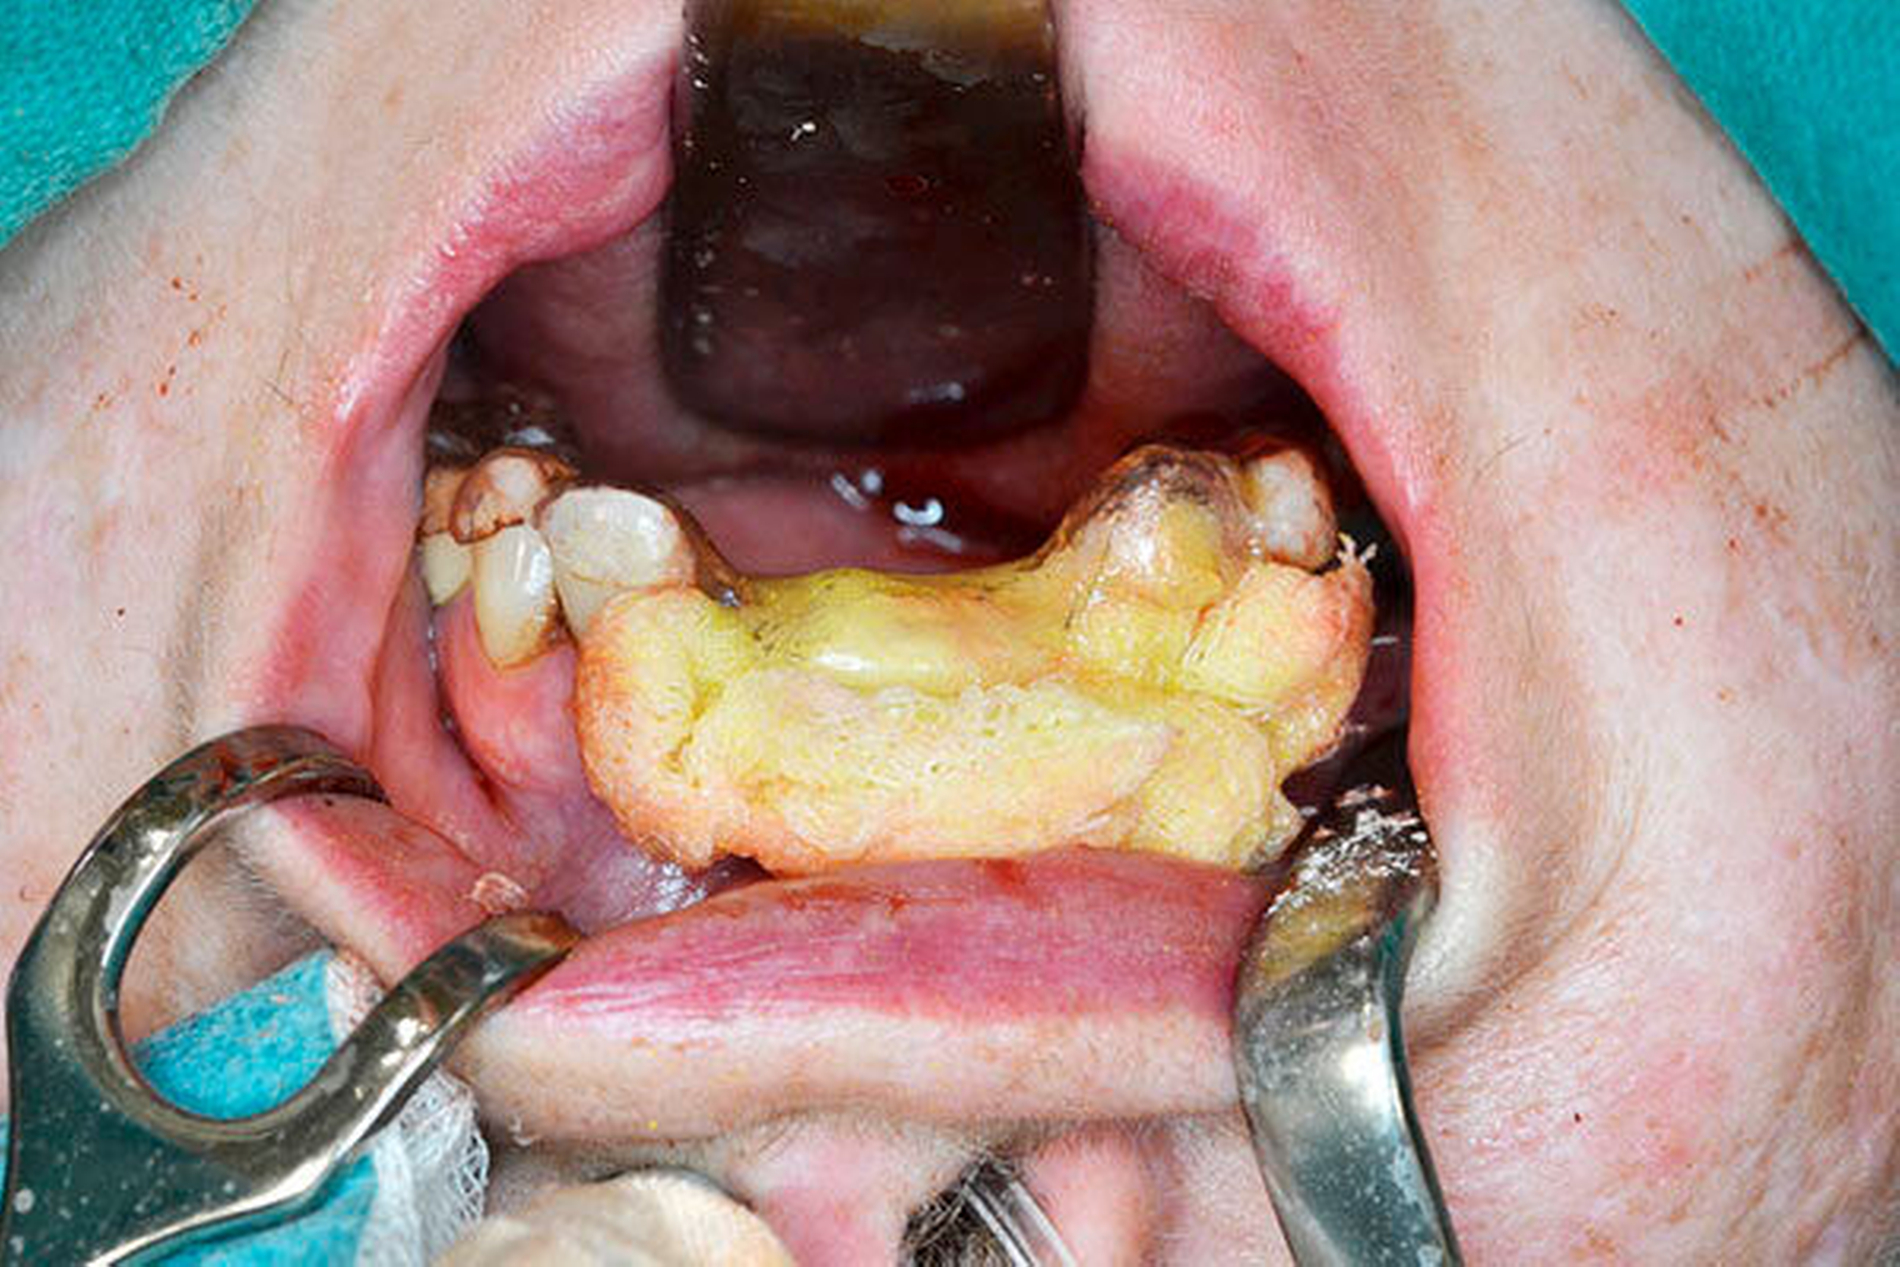

Nach erfolgter Tetrazyklinmarkierung mit Doxycyclin 100 mg 1–0–0 für fünf Tage und präoperativer Abdrucknahme für eine Oberkieferverbandsplatte wurde der Eingriff in Intubationsnarkose durchgeführt. Nach marginaler Schnittführung wurden die Zähne 21, 12 und 13 entfernt sowie eine aufwendige modellierende Osteotomie im Sinne einer partiellen Resektion des Alveolarfortsatzes unter Schwarzlichtkontrolle in diesem Bereich durchgef ü hrt (Abbildung 5).

Die Weichgewebsdeckung des entstandenen Defekts erfolgte mittels Mukoperiostlappen und einer Dreiecksaustauschplastik aus dem Oberkiefervestibulum (Abbildung 6). Nach spannungsfreiem, speicheldichtem Wundverschluss wurde eine Verbandsplatte mittels Jodoformvaseline durch eine Schraube am Gaumen knöchern fixiert (Abbildung 7). Daran schloss sich ein fünftägiger stationärer Aufenthalt unter strikter Ernährung mittels Magensonde sowie breiter intravenöser antibiotischer Abdeckung durch Clindamycin 600 mg 1–1–1 an.